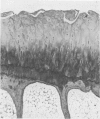

Images in this article